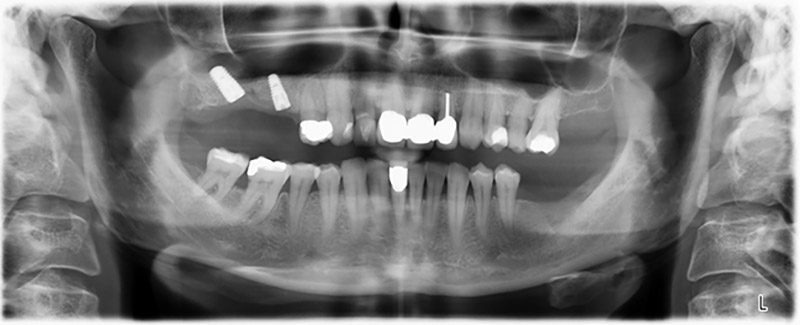

Ortopantomografía

Imagen 20: Ortopantomografía después del tratamiento